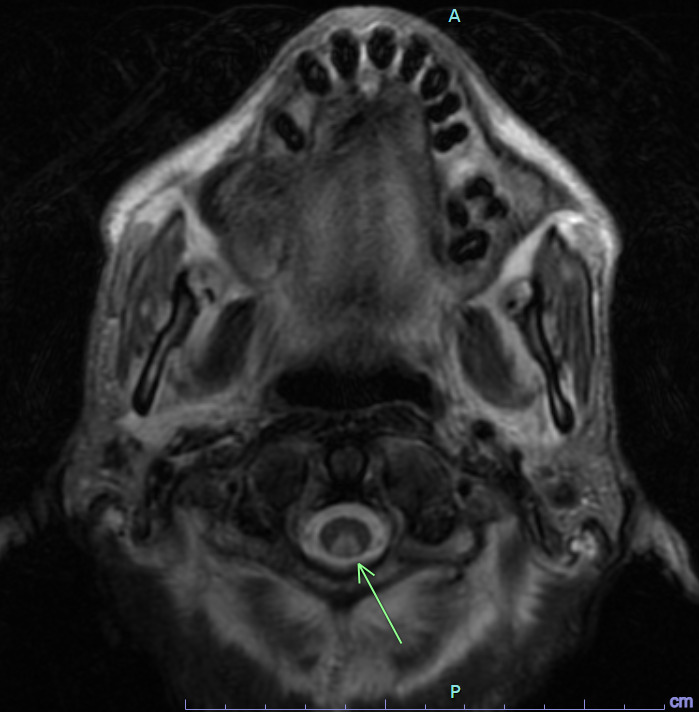

spinal schwannoma

arise from spinal nerve roots

homogeneous enhancement

differentiated from spinal meningioma by lack of dural tail

spinal meningioma

well circumscribed

dural attachment (dural tail sign)